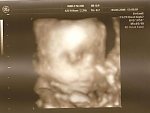

Byliśmy na USG 3D w czwartek

jest śliczna! Pani Doktor całe badanie się zachwycała jaka jest cudna! Uśmiechała się, ziewała, robiła minki i ciągle ruszała buzią

A tutaj pozujemy z rączką

Niewyraźne, bo zrobiłam zdjęcia zdjęć

A tu zeskanowane:

Tutaj widać, ze Dziewczynka